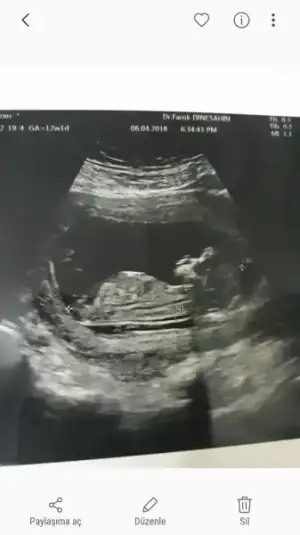

Kız gibi geldi :)Cinsiyet tahmini yaparmisiniz bugun ikili testim vardi cok sukur iyu cikti

Kız değişebiliyo ama erkek olunca sanki daha kesine yakın. Hakkımızda hayırlısı inşallahDoktor bi kız bi erkek dedi bakalim

Kız gibi geldi banaCinsiyet tahmini yaparmisiniz bugun ikili testim vardi cok sukur iyu cikti